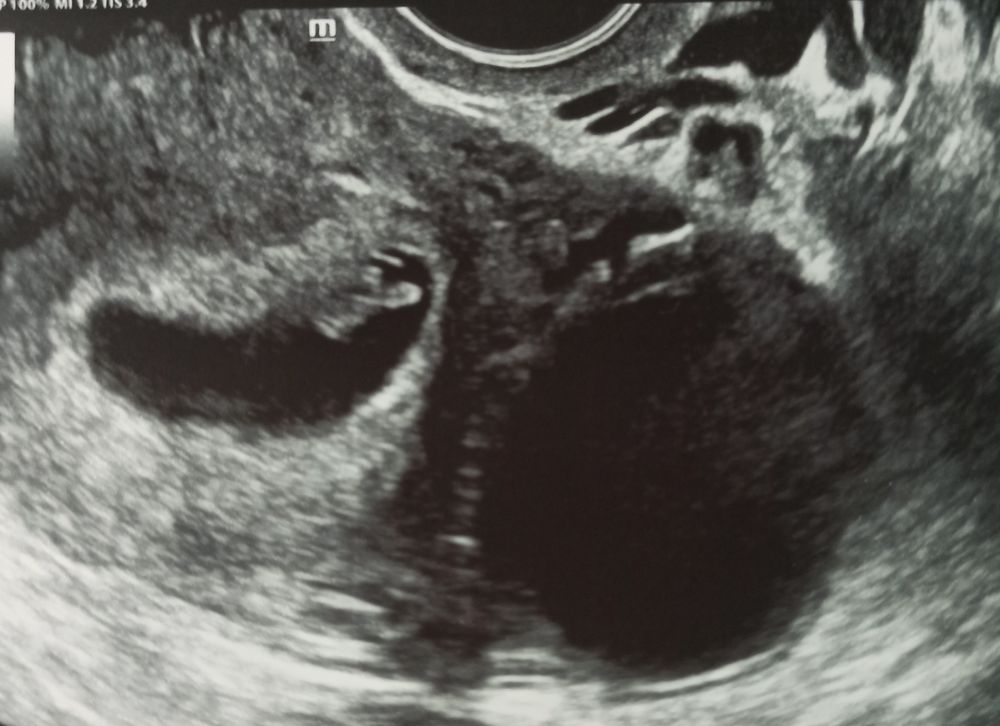

УЗИ на 34 дпо (6+6) ❤🤞🤞🤞

Сходили на УЗИ вместе с мужем, он счастлив🥰 сегодня 20 марта на 34 дпо (6+6):

ПЯ 25 мм, ЖМ 3 мм, КТР 9 мм, ЧСС 141 уд/мин, киста ЖТ 41*36 мм. Врач сказал, что прикрепление плаценты по передней стенке в центре в дне матки, так что не знаю как по методу Рамзи смотреть, по фото плацента сверху слева, может мальчик👦❤ это было бы здорово 👍 Позже сдам анализ на определение пола плода по крови матери. Токсикоз продолжается: тошнит от голода, после еды тяжесть и отрыжка, приходится есть каждые 2 часа понемногу, надеюсь ещё недельку и пройдëт, как и в другие беременности токсикоз был с 5 по 8 неделю, сейчас хочется мясное, острое, солёное, кислое, а вот на сладкое не тянет, может позже вернётся тяга к сладостям. Хотела посмотреть прогестерон и до кучи для архива сдала сегодня и ХГЧ: